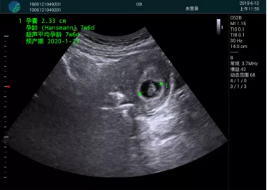

清晰顯示孕囊,通過(guò)軟件包計(jì)算孕齡7w+6d

M20實(shí)時(shí)引導(dǎo),術(shù)中清晰顯示孕囊被破壞和抽吸針的過(guò)程,清晰顯示吸引針

抽吸結(jié)束后縱切子宮,孕囊已被完全抽吸,未見(jiàn)明顯殘留

橫切子宮,發(fā)現(xiàn)右側(cè)宮腔靠近宮角處有少許脫模樣殘留

M20引導(dǎo)下,抽吸針找到右側(cè)宮角處再次清掃

二次抽吸后再次進(jìn)行超聲檢查,宮腔未見(jiàn)殘留,宮腔線(xiàn)清晰顯示